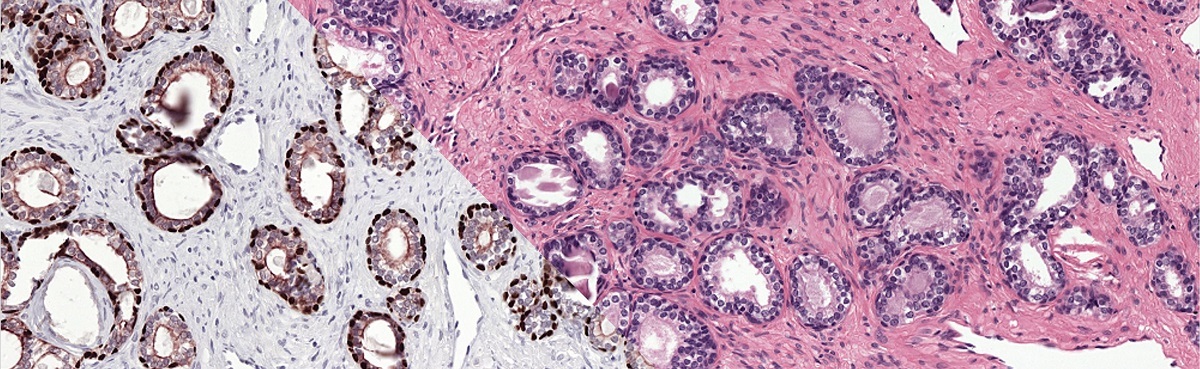

Example from the PESO dataset. The dataset consists of full whole-slide images.

Example of the ground truth segmentation of the epithelium tissue.